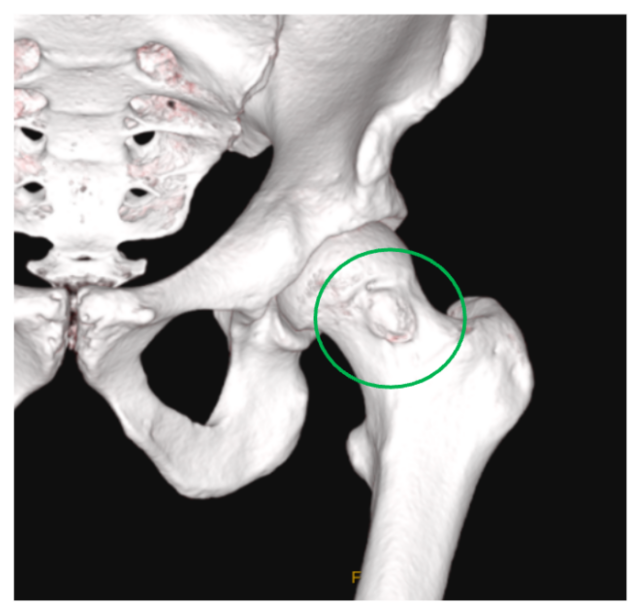

Athletes with Hip Dysplasia: current understanding, management and future directions 🏃🏽♂️🤸♀️ New Editorial in British Journal of Sports Medicine (BJSM) bjsm.bmj.com/content/early/… Huge thanks to my co-authors: Andrew Wallis Dr Joshua Heerey Julie S Jacobsen Jit Balakumar Dr Joanne Kemp Lisa Tønning & Inger Mechlenburg